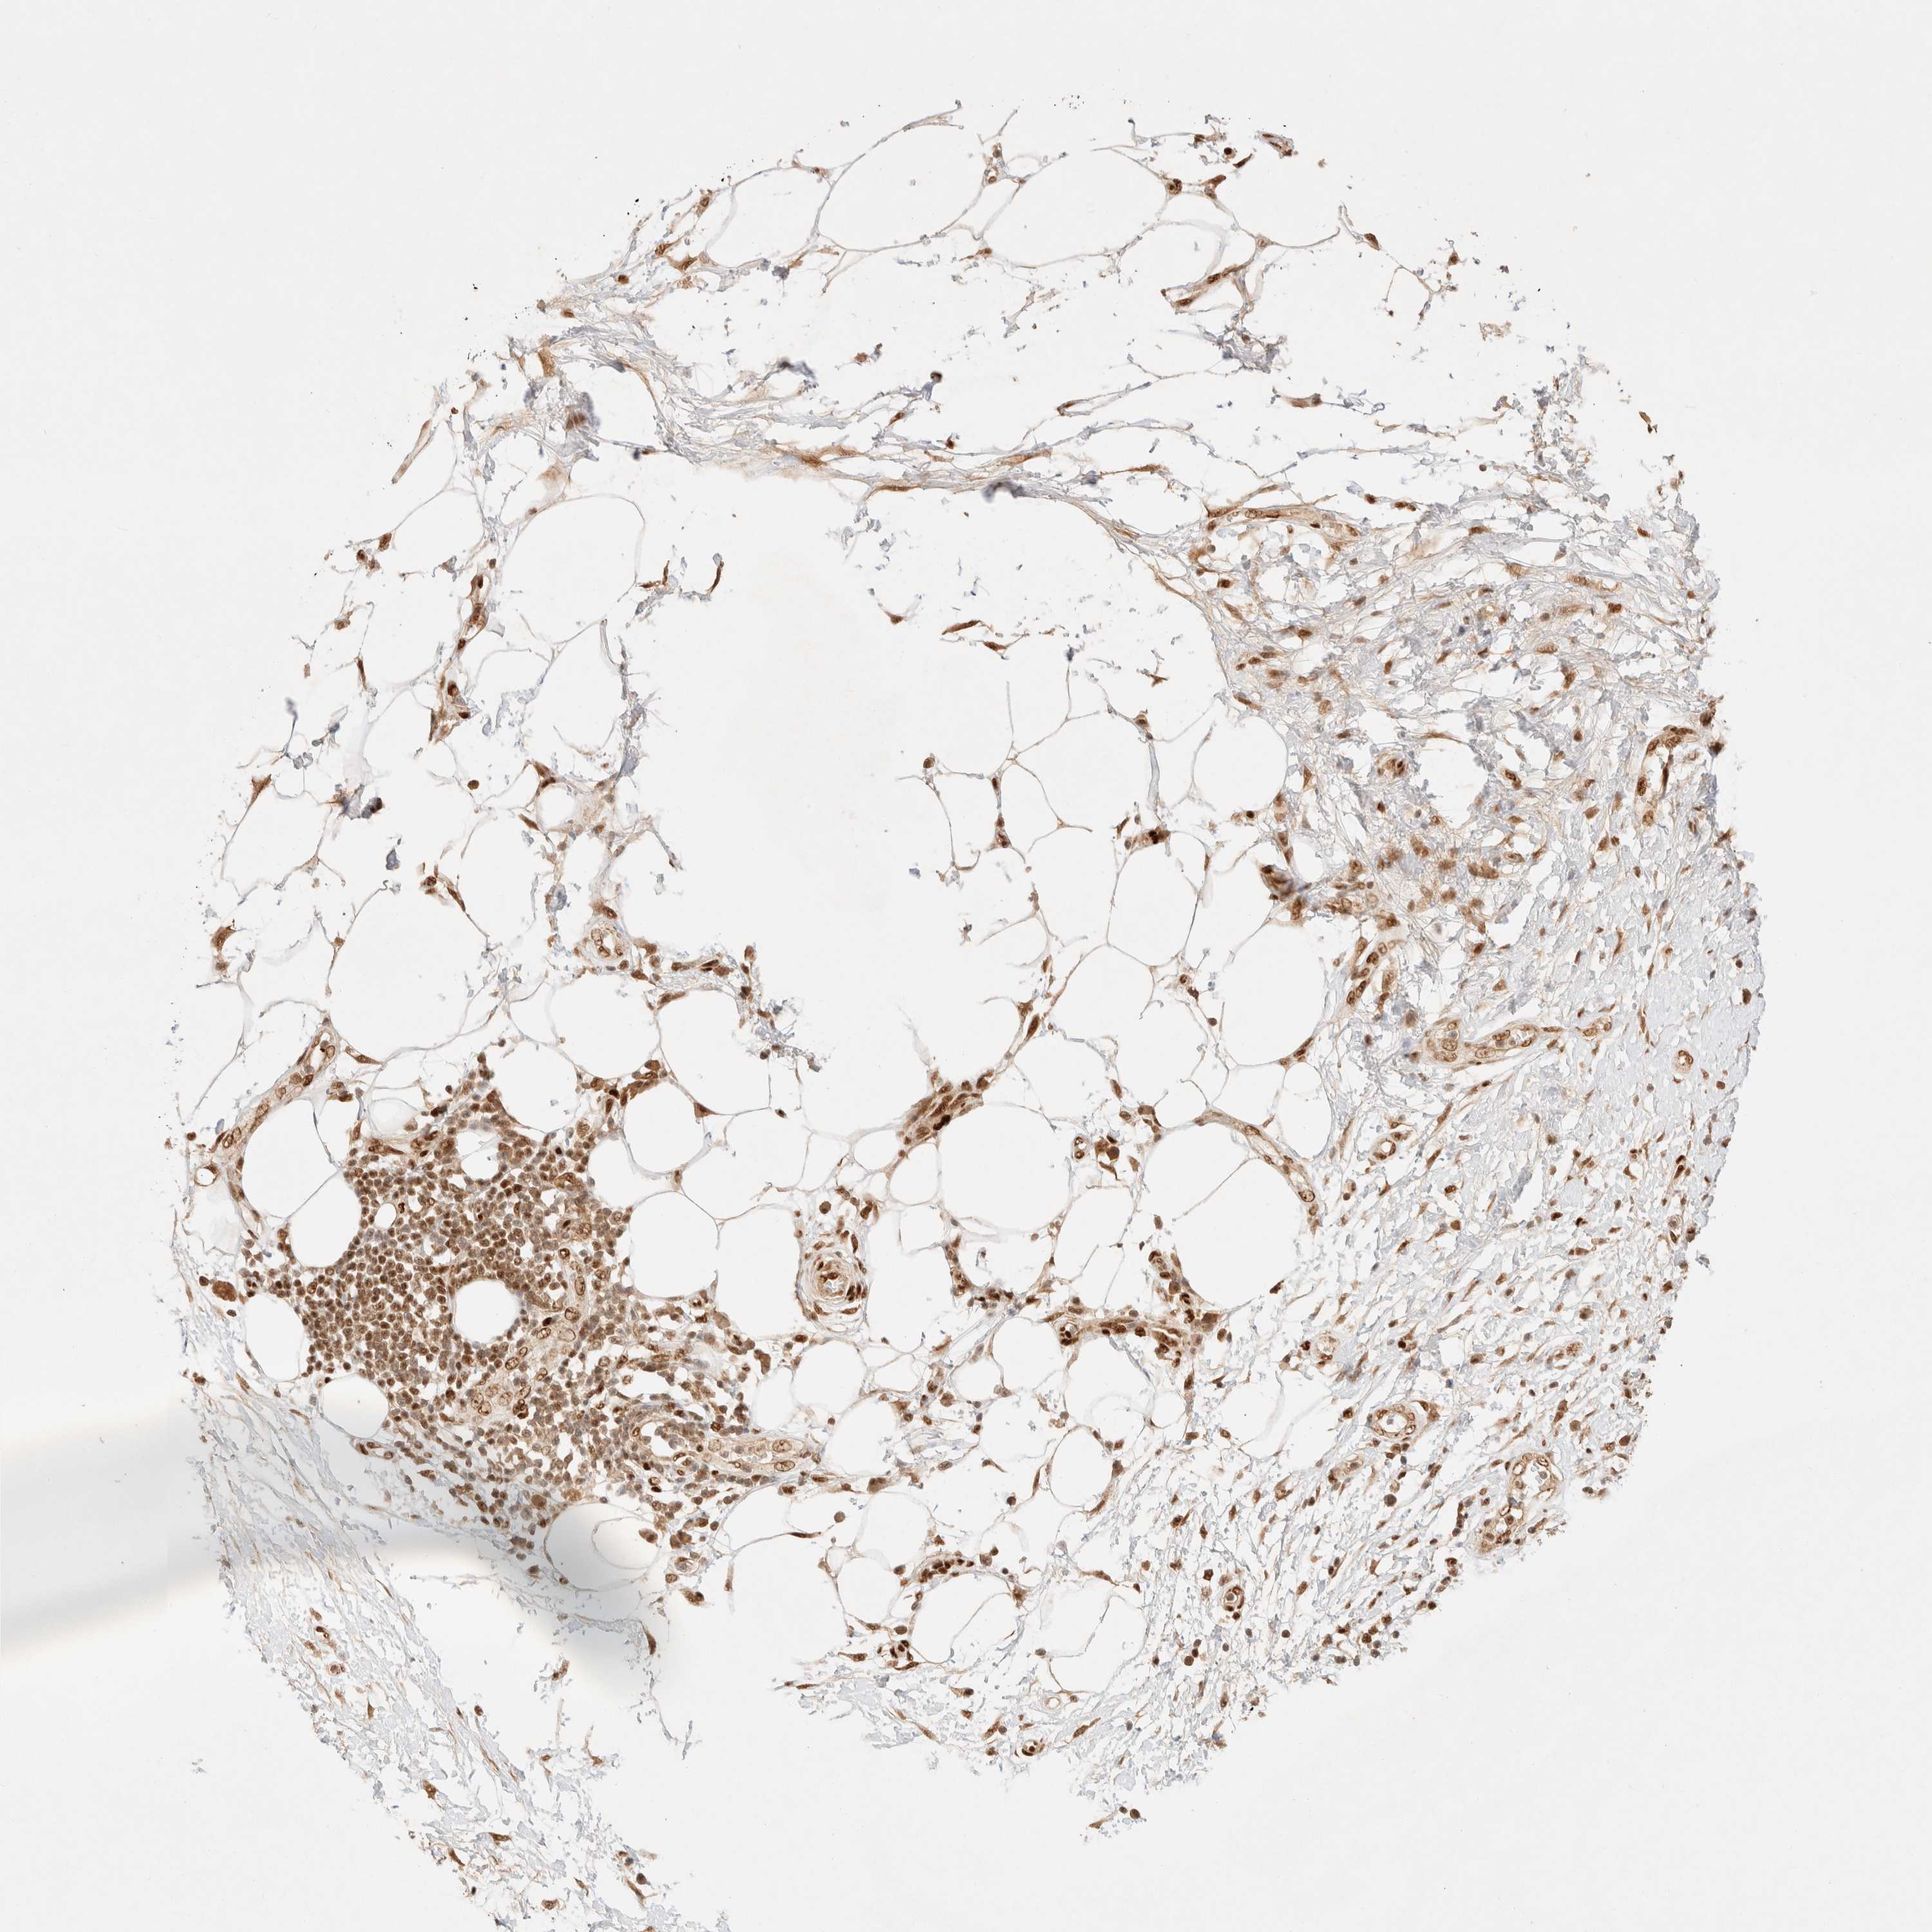

PANCREATIC CANCER - Protein expressioni

A mouse-over function shows sample information and annotation data. Click on an image to view it in a full screen mode. Samples can be filtered based on level of antibody staining by selecting one or several of the following categories: high, medium, low and not detected. The assay and annotation is described here.

Note that samples used for immunohistochemistry by the Human Protein Atlas do not correspond to samples in the TCGA dataset.

Antibody stainingi

Antibody staining in the annotated cell types in the current human tissue is reported as not detected, low, medium, or high, based on conventional immunohistochemistry profiling in selected tissues. This score is based on the combination of the staining intensity and fraction of stained cells.

Each image is clickable and will lead to virtual microscopy that enables deeper exploration of all samples and also displays staining intensity scores, fraction scores and subcellular localization as well as patient and tissue information for each sample.

Antibody HPA024630

Staining

High

Medium

Low

Not detected

Intensity

Strong

Moderate

Weak

Negative

Quantity

>75%

75%-25%

<25%

None

Location

Nuclear

Cytoplasmic/membranous

Cytoplasmic/membranous,nuclear

Adenocarcinoma, NOS